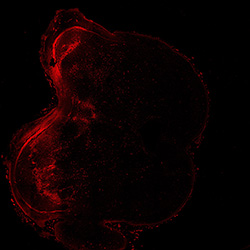

An anatomical analysis of the developing human midbrain from 6 post-conceptional weeks (PCW) to 22 PCW reveals increased tissue complexity, characterized by the emergence of dopaminergic nuclei, as highlighted by immunofluorescence analysis for tyrosine hydroxylase (TH).

TH

13PCW human midbrain

22PCW human midbrain